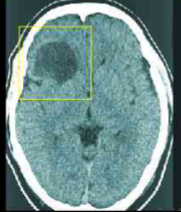

snowman configuration

what is the classic MRI sign of a pituitary macroadenoma on MRI?

snowman (pituitary macroadenoma)